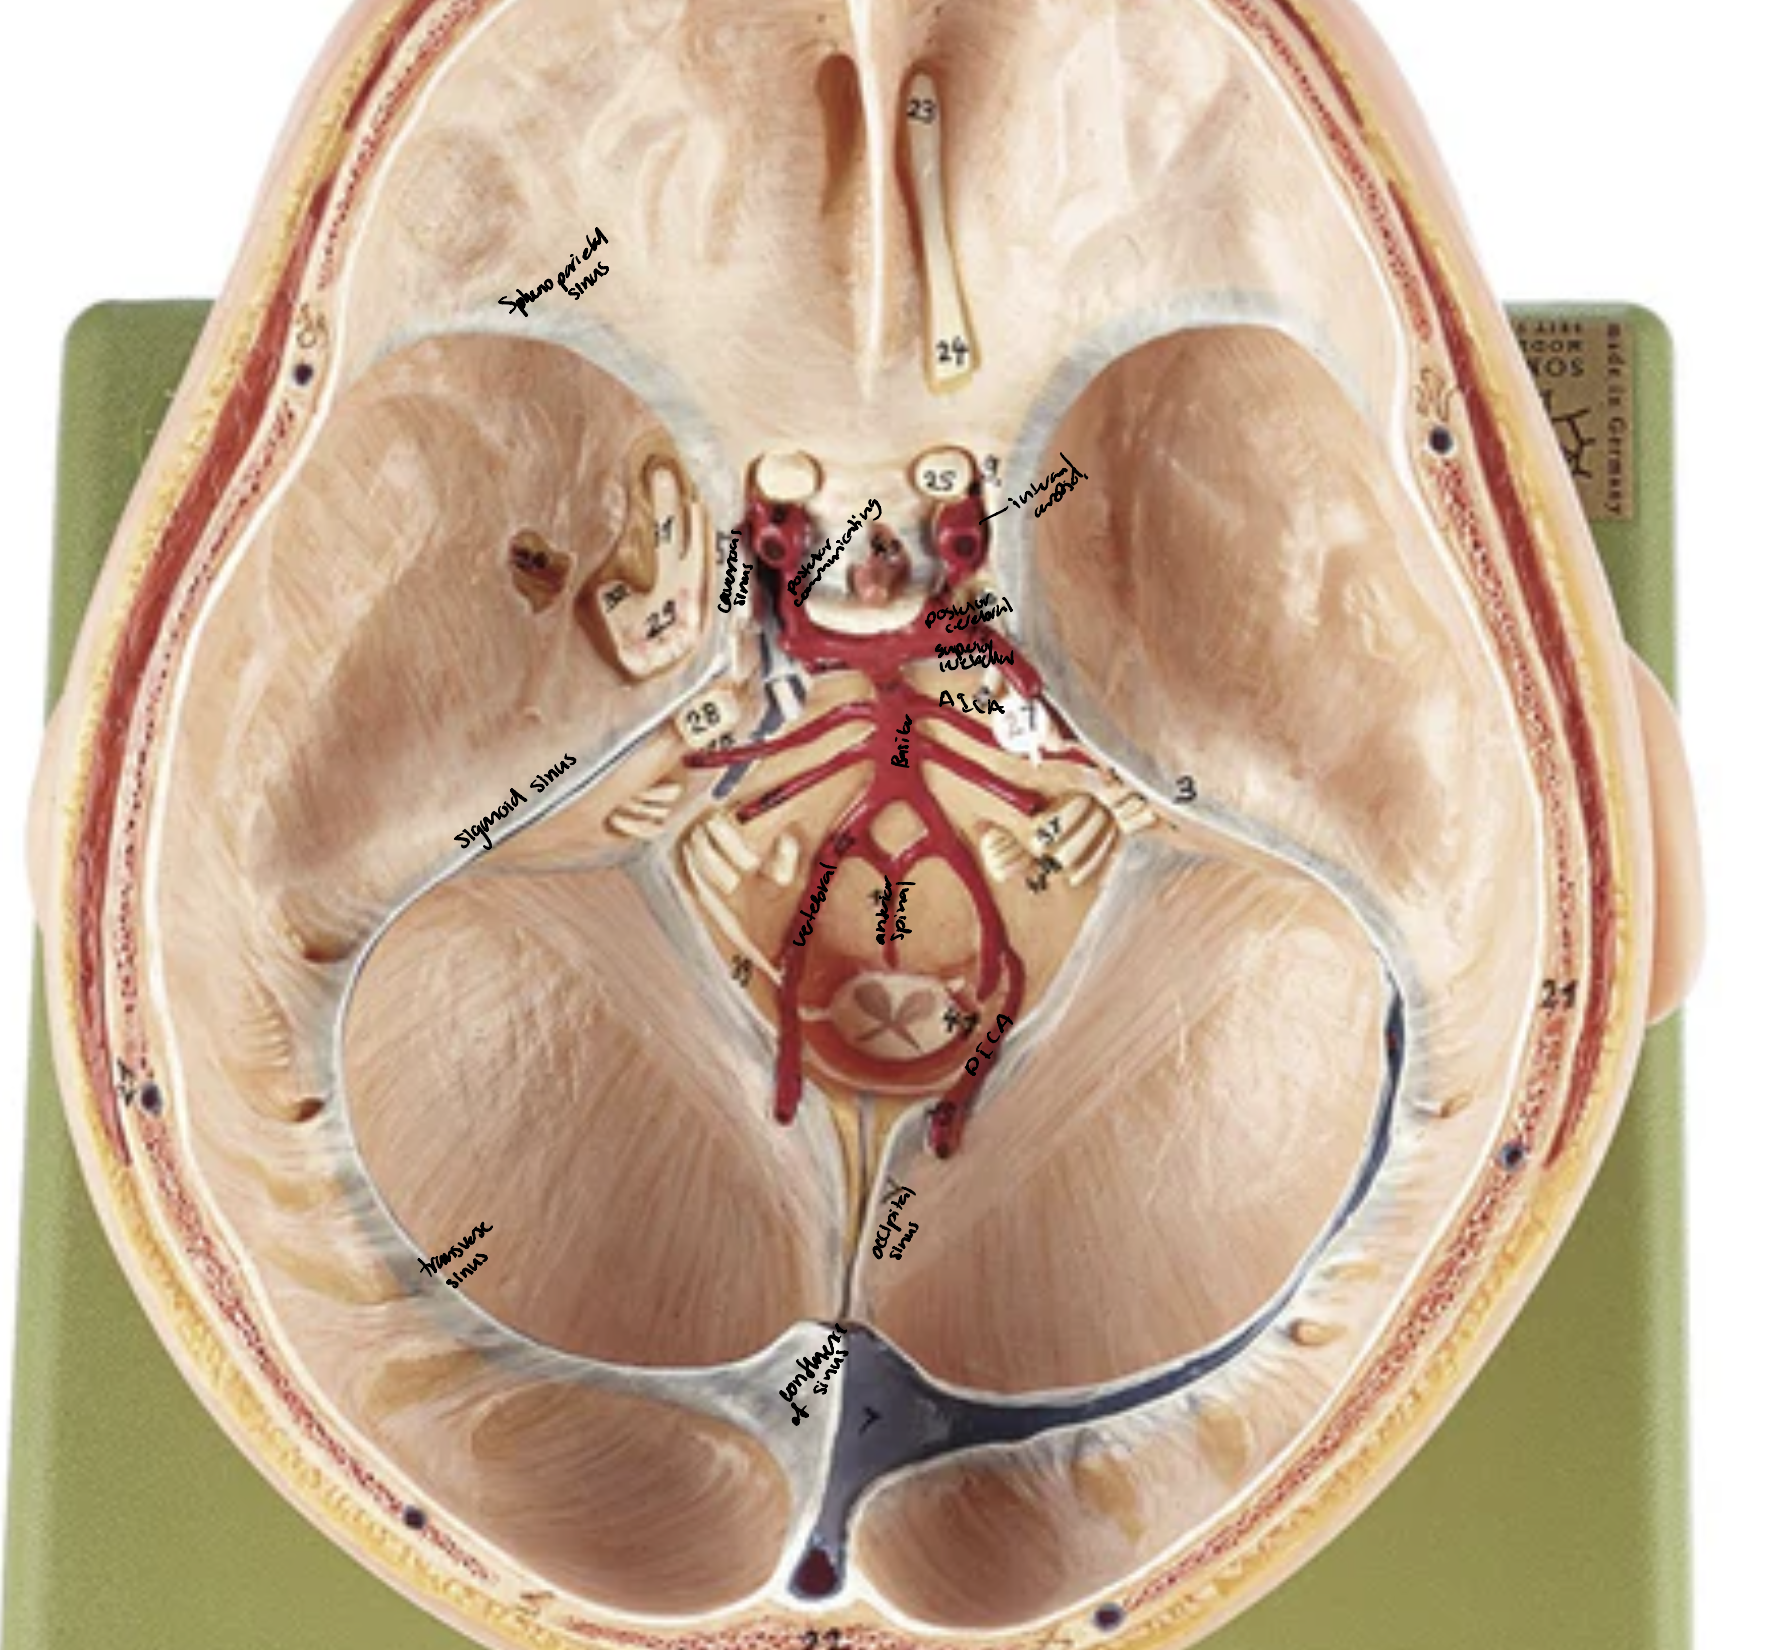

Superior sagittal sinus

Straight sinus

Confluence of sinuses

Transverse sinuses

Sigmoid sinuses

Cavernous sinuses

Intercavernous sinus

Superior petrosal sinuses/inferior petrosal sinuses

Occipital sinus

Sphenoparietal sinuses